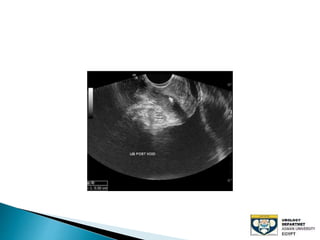

The document discusses urinary tract stones, detailing their types, causes, symptoms, and diagnostic methods. It highlights the risk factors such as infections and obstructions, with men being more commonly affected. Treatment options include various surgical methods, particularly for managing bladder outflow obstruction and lithiasis.